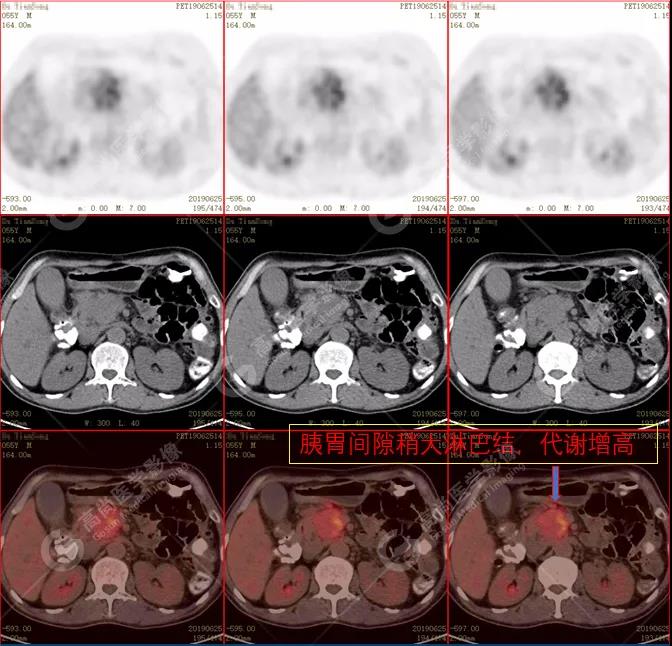

(2)胰周(胰胃間隙)稍大淋巴結(jié),代謝增高。

PET/CT診斷

自身免疫性胰腺炎,伴胰周淋巴結(jié)炎性增生。